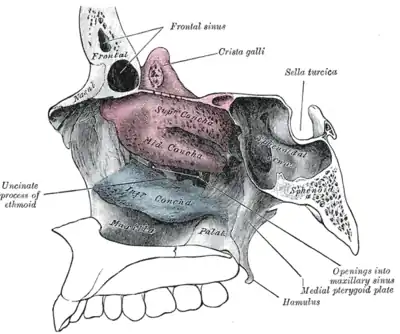

Les cavités nasales ou fosses nasales sont deux espaces séparés par une cloison : le septum nasal. Elles sont situées :

- au-dessus de la cavité buccale ;

- au-dessous de la cavité crânienne ;

- en dedans des cavités orbitaires et des sinus maxillaires ;

- en avant du rhinopharynx.

Limites

Les fosses nasales sont limitées par :

- l'orifice piriforme en avant,

- l'orifice choane en arrière,

- l'os nasal et l'ethmoïde en haut,

- le maxillaire, l'ethmoïde et le cornet nasal inférieur latéralement,

- le palais (os maxillaire et os palatin), qui les sépare de la cavité buccale.

À l'origine cavité unique chez les vertébrés primitifs, la cavité est séparée médialement en 2 fosses par une cloison verticale, le septum nasal, constitué des os vomer et ethmoïde.

Les fosses nasales sont prolongées en avant par le nez et en arrière par le pharynx.

Les sinus paranasaux sont reliés aux fosses nasales par des petits orifices appelés ostia.

Sur les côtés latéraux on a trois cornets qui offrent une résistance à l'écoulement de l'air et le dirigent vers l'épithélium olfactif en haut.

Il y a trois cornets dans chaque cavité nasale :

- le cornet inférieur : le plus grand, aussi long que l'index;

- le cornet moyen : aussi long qu'un auriculaire ;

- le cornet supérieur : très petit.

Les deux cavités nasales sont séparées par la cloison nasale appelée septum.